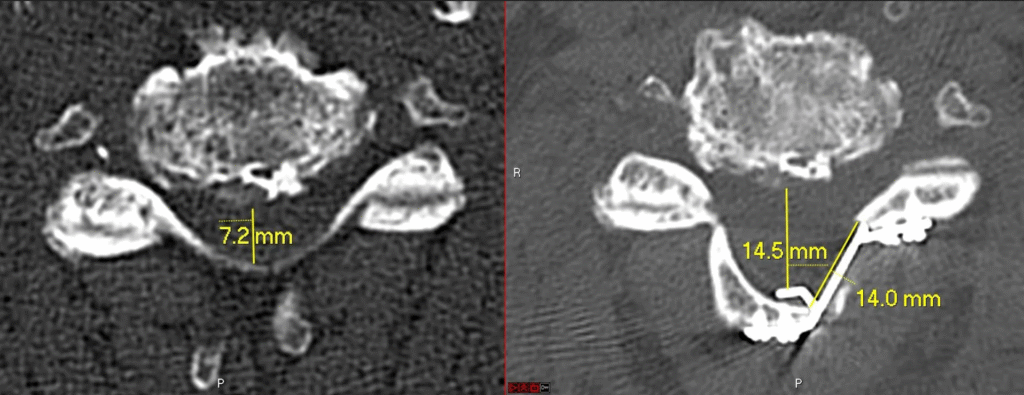

C1-2 fusion

Posterior Cervical Fusion